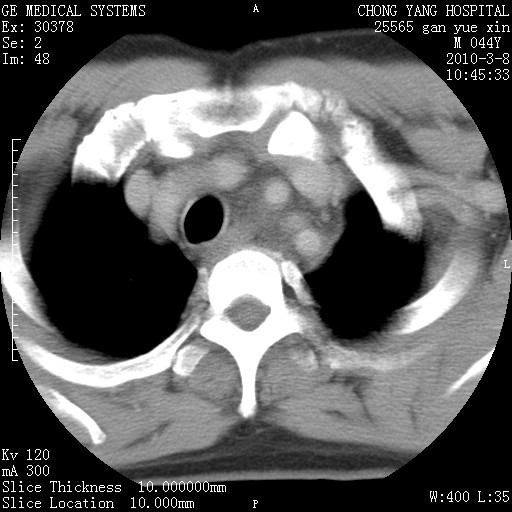

标题: CT24940:主动脉增强,典型病例。 [打印本页]

标题: CT24940:主动脉增强,典型病例。

夹层动脉瘤。

夹层动脉瘤,典型

主动脉夹层。

动脉夹层的分型:

⒈debakey分型:根据主动脉夹层累及部位,分为三型:ⅰ型:原发破口位于升主动脉或主动脉弓部,夹层累及升主动脉、主动脉弓部、胸主动脉、腹主动脉大部或全部,少数可累及髂动脉。ⅱ型:原发破口位于升主动脉,夹层累及升主动脉,少数可累及部分主动脉弓。ⅲ型:原发破口位于左锁骨下动脉开口远端,根据夹层累及范围又分为ⅲa,ⅲb。ⅲa型:夹层累及胸主动脉。ⅲb型:夹层累及升主动脉、腹主动脉大部或全部。少数可累及髂动脉。

⒉stanford分型:a型:夹层累及升主动脉,无论远端范围如何。b型:夹层累及左锁骨下动脉开口以远的降主动脉。

夹层动脉瘤,少量胸水

夹层动脉瘤;左侧少量胸腔积液。